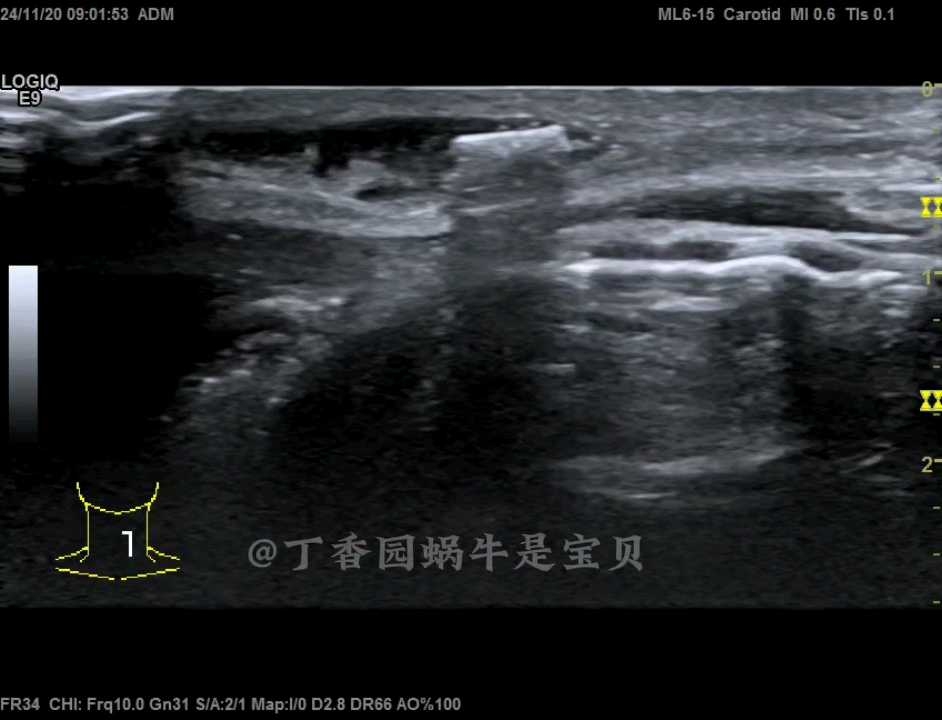

男性,自述从事装修工作中,钉钉子发生事故,当时墙面石头等向脸上飞过来,当时颈部出血多,四天后红肿还是不退,来医院,检查过程中我对强回声有疑惑,怀疑异物,让他描述当时的工具钉子都是什么样的,他说有个炮钉,但是他说钉子不会断,钉子上有个帽,该患者后续我会随访。